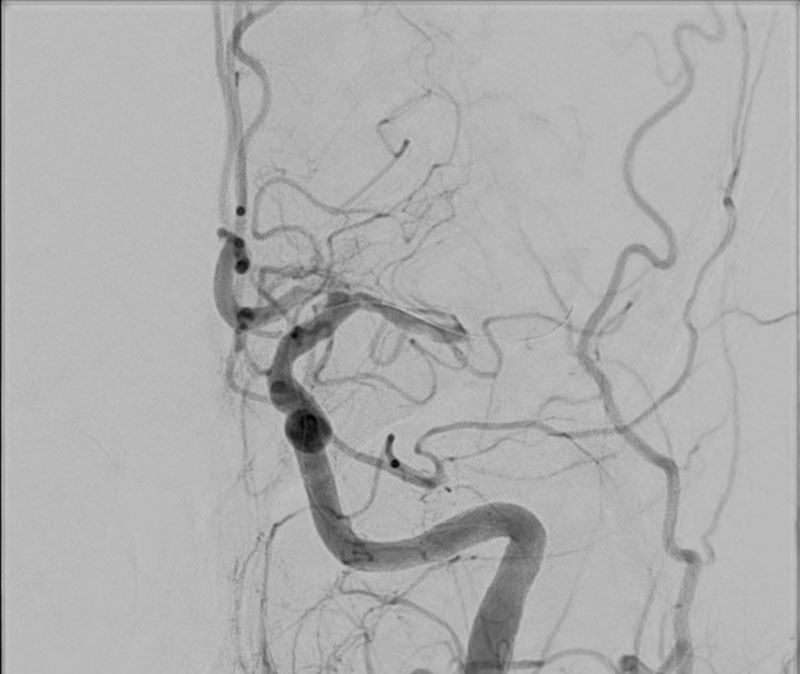

VASO-CT post

24h CT-scan

24h CTA and CTP

6 months DSA follow up